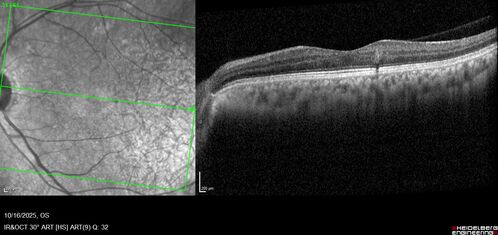

Perivascular Exudative Vascular Complex - Perifoveal Microaneurysm

59 year old man - asymptomatic - not diabetic